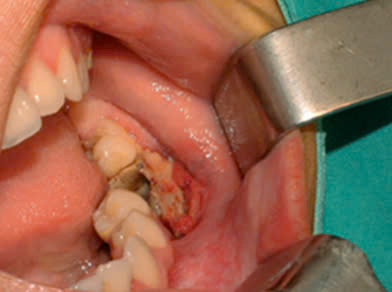

– Trong nha khoa, việc sử dụng arsenic có thể gây những biến chứng như: Hoại tử xương hàm; Hoại tử mô mềm, hoại tử lợi; Viêm tủy xương hàm…

Hình 2: Viêm tủy xương hàm tại vị trí răng 36 sau điều trị nội nha và được nhổ bỏ6

Điểm chung của những ca lâm sàng này là bệnh nhân sử dụng arsenic trong điều trị tủy để giảm đau nhưng khi ra về bệnh nhân gặp phải cơn đau dữ dội và phải quay lại phòng khám để nhổ răng. Tuy nhiên, tình trạng tổn thương đã lan ra ngoài xương hàm.